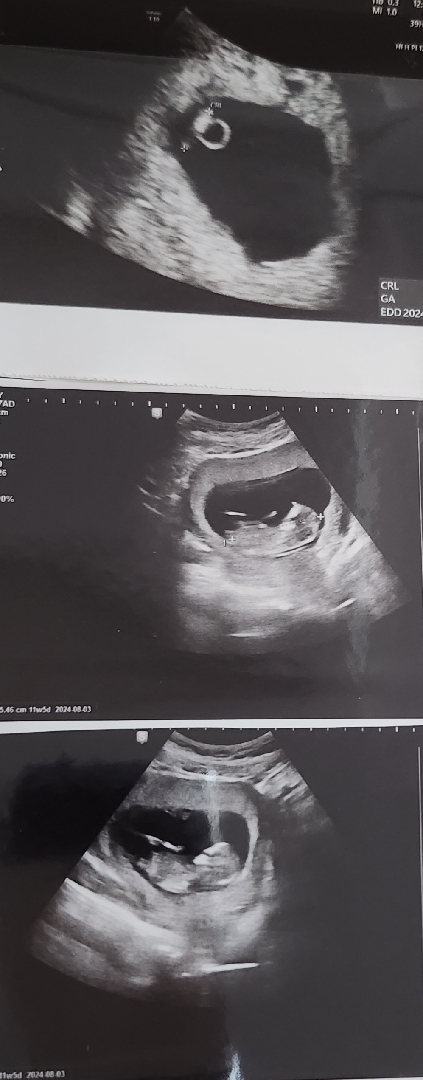

아들일지 딸일지 너무 궁금해요

입덧이나 태몽은 딸인것같은데 난황위치는 아들인것같구 각도법은 아예 볼줄 모르겠어서 한번 여쭤봐요 아들일지 딸일지 눈썰미 좋으신분들의 답변 부탁드려요!!